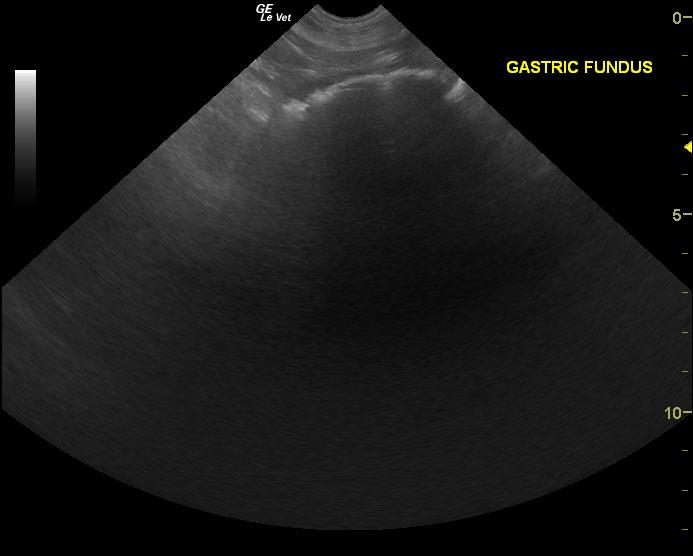

An 8-year-old FS Great Dane dog with a history of urinary tract infection and VPCs was presented for evaluation of lethargy and weakness in the hind limbs. Elevated ALP activity and BUN was present on serum biochemistry.

An 8-year-old FS Great Dane dog with a history of urinary tract infection and VPCs was presented for evaluation of lethargy and weakness in the hind limbs. Elevated ALP activity and BUN was present on serum biochemistry.